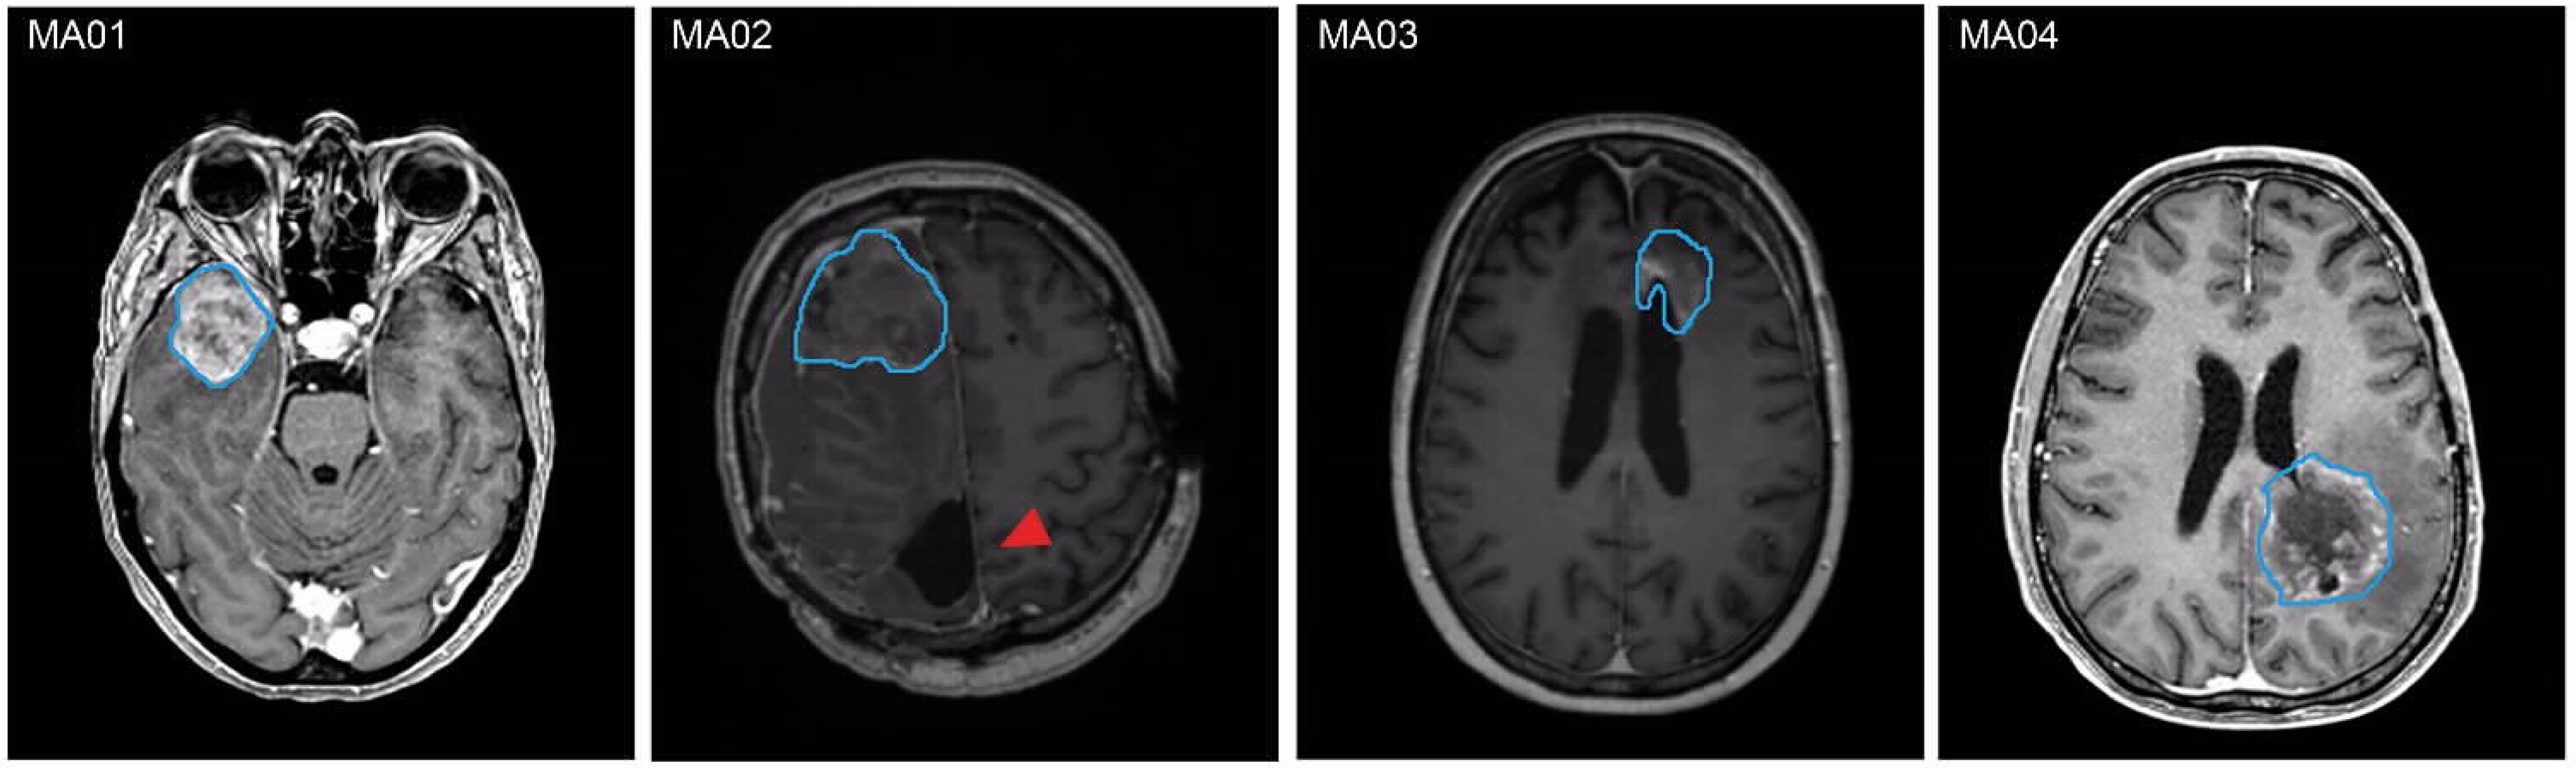

| Patient ID | Weight of Tumor Tissue (g) a | Pattern of Tumor Progression b | Diagnosis | Ki67 | Time Until Lab Report (Days) |

|---|---|---|---|---|---|

| MA01 | 9.15 | Distant | GB WHO grade 4 MGMT methylated, IDH wt | 40% | 14 |

| MA02 | 3.42 | Distant | GB WHO grade 4 MGMT methylated, IDH wt | 0% | 13 |

| MA03 | 8.97 | Local | GB WHO grade 4 MGMT methylated, IDH wt | 2% | 15 |

| MA04 | 16.16 | Distant | IDH mut astrocytoma grade 4 | 70% | 19 |